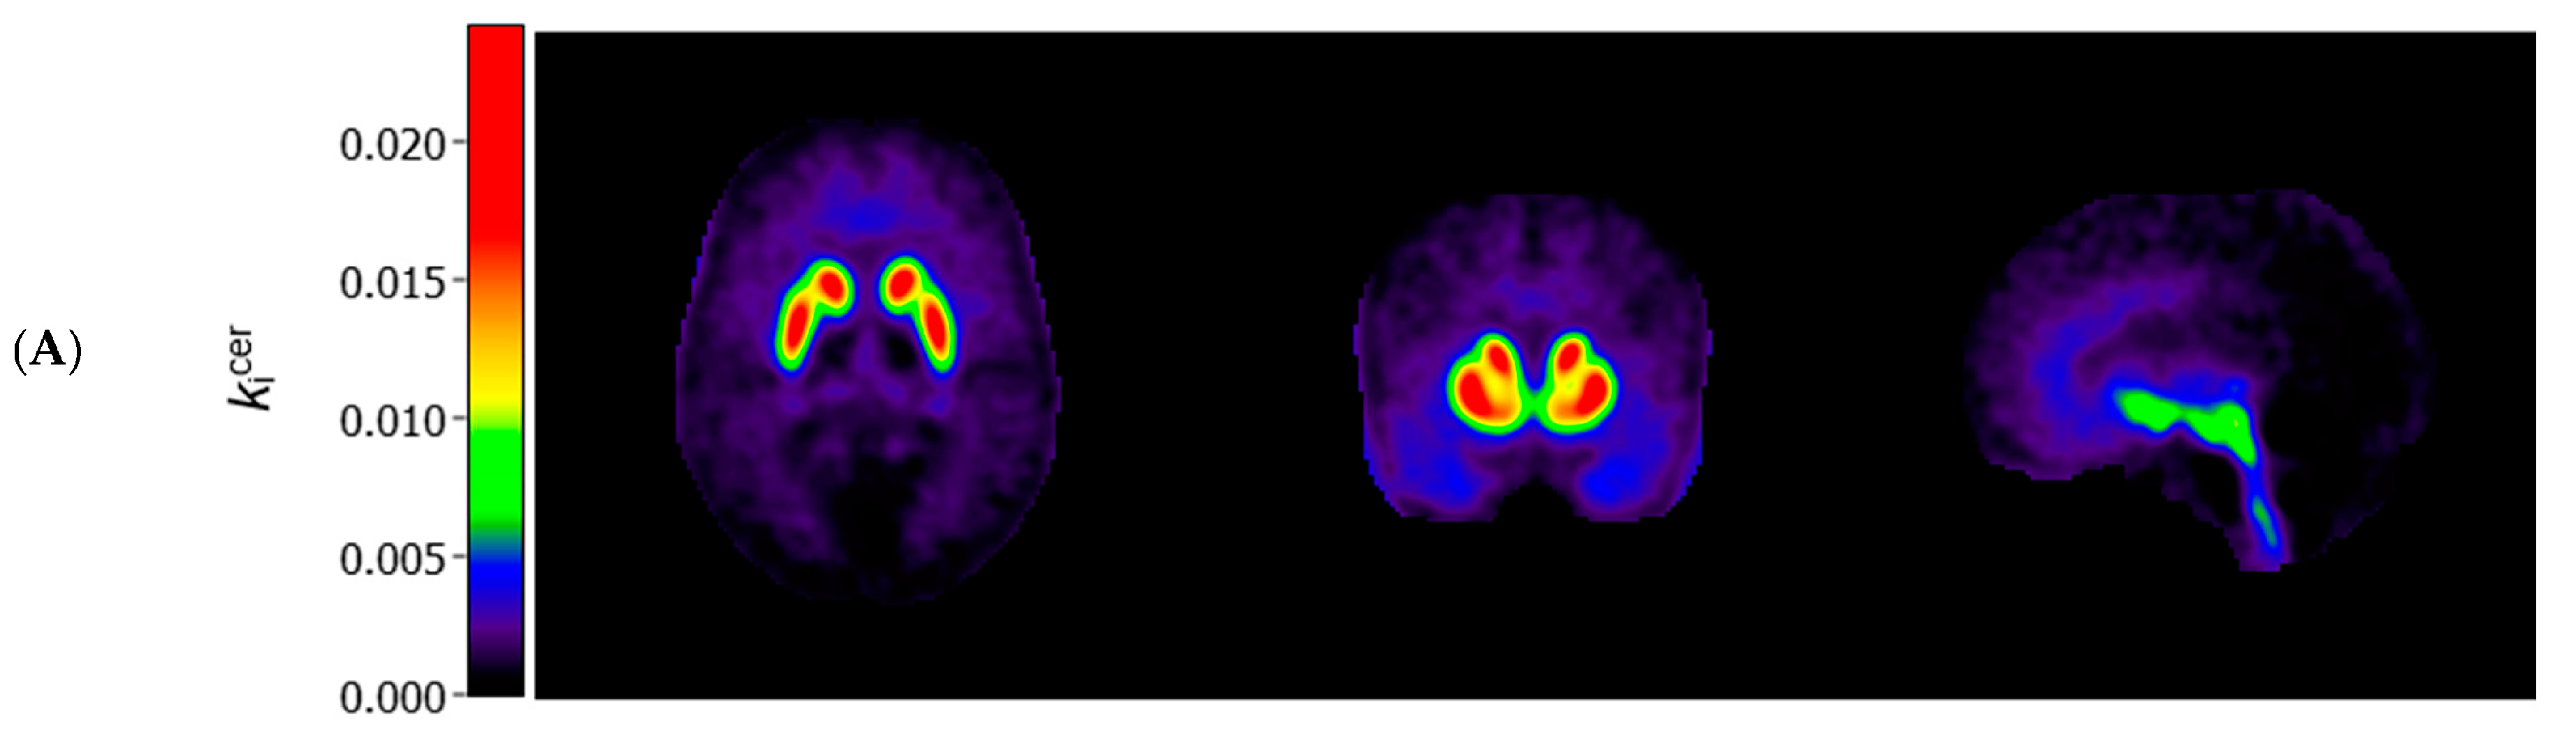

3.3. Voxel-Based Comparisons